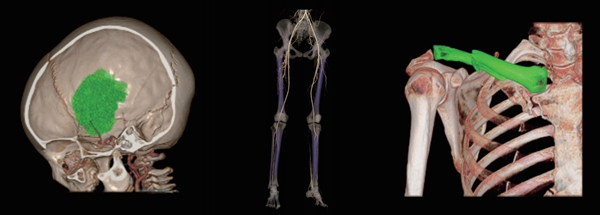

传统CT只能分辨物质密度差异,而能谱CT则可以识别物质成分差异,从而对疾病做出更准确的定性、定量分析。该设备支持16cm宽体能谱扫描,通过KV切换采集高低能数据,并根据不同物质不同能量下的衰减差异,获得组织中物质成分和能谱特征的定性及定量分析结果。常用于判定肿瘤的同源性、泌尿系结石成份分析、痛风石能谱成像等。

【痛风石能谱成像】